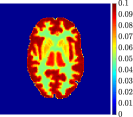

Figure 4, Figure 5, and Figure 6 show the mean images computed over the ten reconstructions obtained by the methods reg-AS-TR, reg-GN, and by the Matlab routine lsqcurvefit implementing a standard Trust-Region-Reflective least-squares algorithm [11, 10]. We used the noise-free IF and the perturbed IF with and of noise, respectively. Figure 7 contains mean and standard deviation values of the kinetic parameters computed over the ten reconstructions and over each one of the four homogeneous regions, for each one of the three noise levels on the IF.

In general, reg-AS-TR and lsqcurvefit seem to provide similar mean reconstructions, although uncertainties associated to lsqcurvefit are significantly bigger. On the other hand reg-GN seems to systematically underestimate the parameter values within region . Furthermore and as expected, for all methods the quality of the parametric reconstructions deteriorates with increasing noise levels; this is more clear from the and parametric images, probably due to the different sensitivities of the data with respect to the model parameters [37]. In reg-GN and lsqcurvefit some artifacts can be observed at the edges of the homogeneous regions, especially around region and region , whereas the effect of regularization in reg-AS-TR results in a reduced presence of artifacts while the structure of the regions is preserved. This general trend is confirmed by the error-bar plots of Figure 7. Finally, the frames in Figure 8 corresponding to reg-AS-TR show a significant improvement of the image quality with respect to what is provided by the other two approaches.